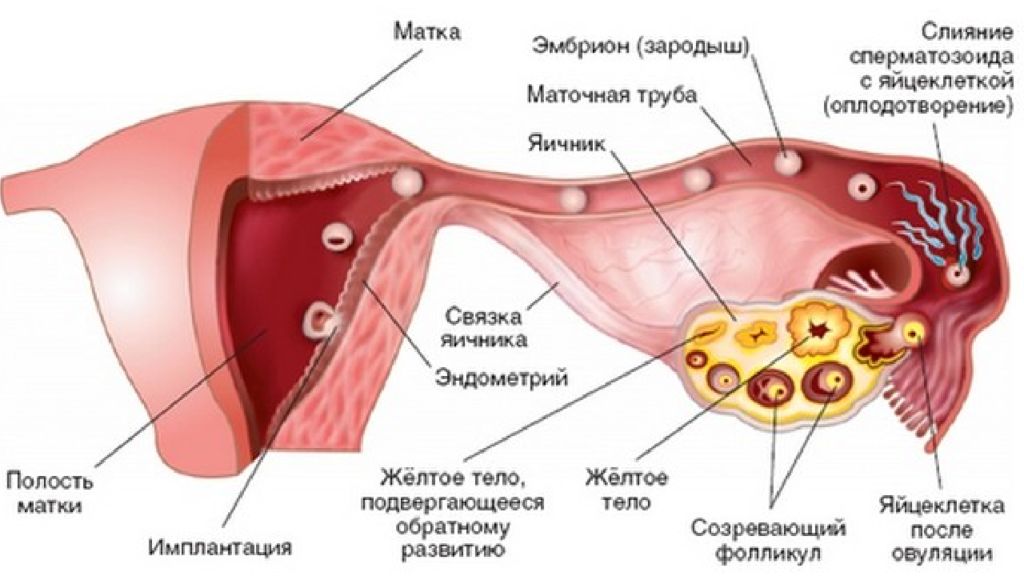

Созревание фолликула в яичнике: этапы и процессы

Раздел: Другие животные